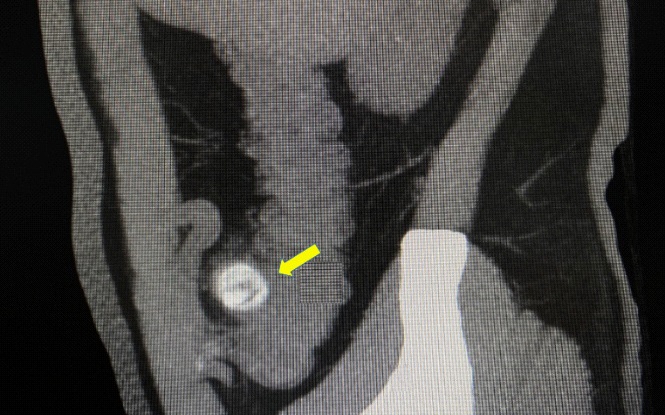

The computed tomography scan of abdomen showed about 20 mm X 20 mm circular high density shadow in right colon, which can be observed in colonic lumen but protruding out of the lumen. Colonoscopy (Figure 3) was also performed and the fecal impaction was identified in the cecal diverticulum above the ileocecal valve. The mucosa surrounding the diverticulum was hyperemic and edema. Than the fecalith was removed successfully with a foreign forceps under colonoscopy. The internal mucosa of the diverticulum was hyperemia, and no perforation was observed (Figure 4). The patient’s abdominal pain were relieved after endoscopic treatment. To prevent recurrence of the disease, surgical removal of the diverticulum was recommended but the patient was hesitant. There was no recurrence of abdominal pain and fecal impaction during 10 months follow-up.

Figure 4: The internal mucosa of the diverticulum was hyperemia, and no perforation was observed after the fecalith was removed.